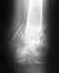

Застарелый краевой перелом

Добрый день, подскажите пожалуйста у меня опухает наружная ладыжка в течении 1,5 года.

Пошла к хирургу меня отправили на рентген. Обнаружили застарелый краевой перелом. В следствии чего он мне доставляет боль.Врач предлагает сделать операцию по удалению обломаного фрагмента или оставить все как есть, говорит ничего страшного нет, подскажите пожалуйста стоит делать операцию? Заранее спасибо.

• Кликните для загрузки файла перелом.jpg